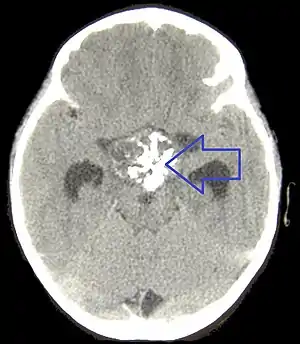

Le craniopharyngiome est une malformation tissulaire embryonnaire (c'est-à-dire apparue avant la naissance) de la région hypophysaire. Les raisons de cette malformation sont encore inconnues. La tumeur, souvent kystique, est visible à l'IRM (imagerie par résonance magnétique) et de nature bénigne. Elle se développe à partir des restes de la poche de Rathke, dans et au-dessus de l'hypophyse. Le craniopharyngiome se situe à proximité directe de zones du cerveau très importantes pour le développement somatique et psychique. La proximité du nerf optique peut aboutir à une réduction du champ visuel, voire une cécité.